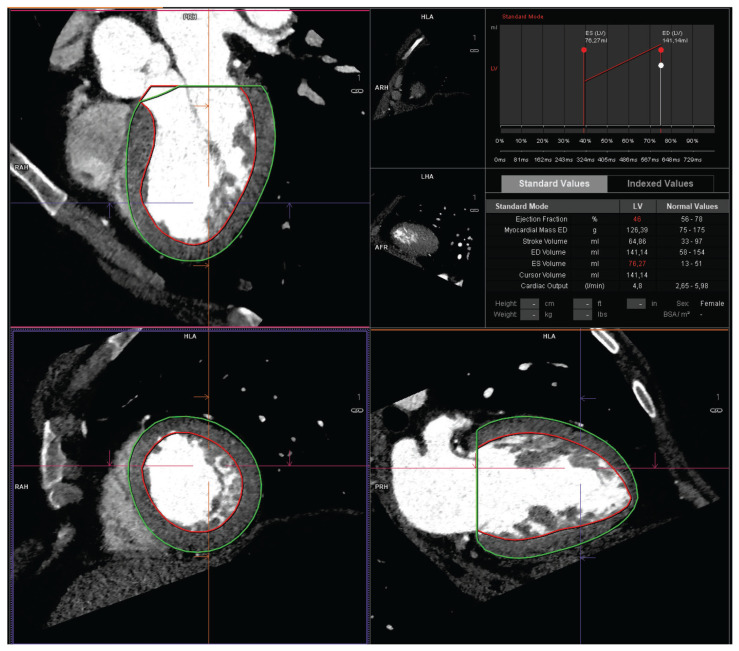

Methods: Out of 426 patients with DCM who underwent computed coronary tomography angiography (CCTA), we identified 34 without signs of coronary atherosclerosis and compared them with 193 consecutive patients without DCM and atherosclerosis in CCTA. They were matched one to three by sex, coronary dominance pattern, and body-surface area (BSA). Left ventricle myocardial mass (LVMM) and proximal and middle coronary artery segment dimensions were evaluated with the use of dedicated, commercially available software.

Results: Overall, coronary segment dimensions were not different between groups except for the medial left anterior descending segment and obtuse marginal, which were wider in the DCM group, while the proximal right coronary artery was larger in the non-DCM group. Total coronary artery volume (CAV) and LVMM/CAV ratio were greater in the DCM group (2879 [2535-3508] mm³ vs. 2521 [2120-3115] mm³, p = 0.03) and (0.062 [0.054-0.074] g/mm³ vs. 0.049 [0.039-0.058] mm³, p = 0.0002), respectively. Also, the LVMM/coronary artery ostial area (COA) ratio was larger in patients with DCM (5.4±1.3 g/mm² vs. 3.7 ± 1.1 g/mm², p < 0.0001). The independent positive predictors of a larger LVMM/CAV ratio were DCM and BSA, while age was a negative predictor. LVMM/COA ratio positive predictors were DCM and male sex.